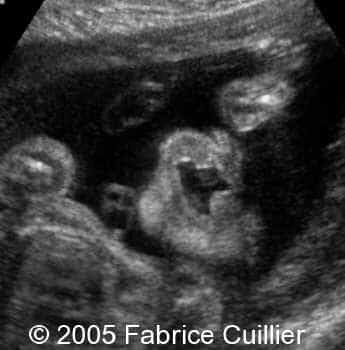

Cleft lip unilateral, 26 weeks

The following are the ultrasound images of a fetus with unilateral cleft lip, discovered at 26 weeks of gestation.